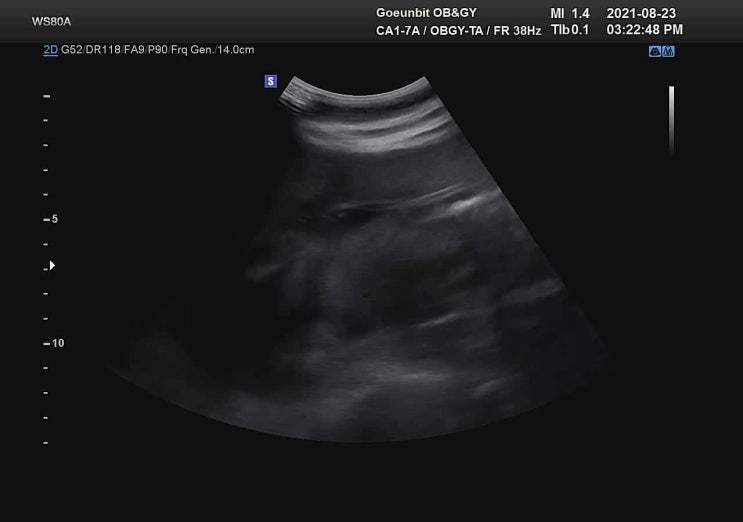

2021. 8. 23. 공포의 임당검사가 있던 날. 태아검진일 휴가를 썼다. 남편 반차 쓰고 같이 갈 줄 알고 넉넉...